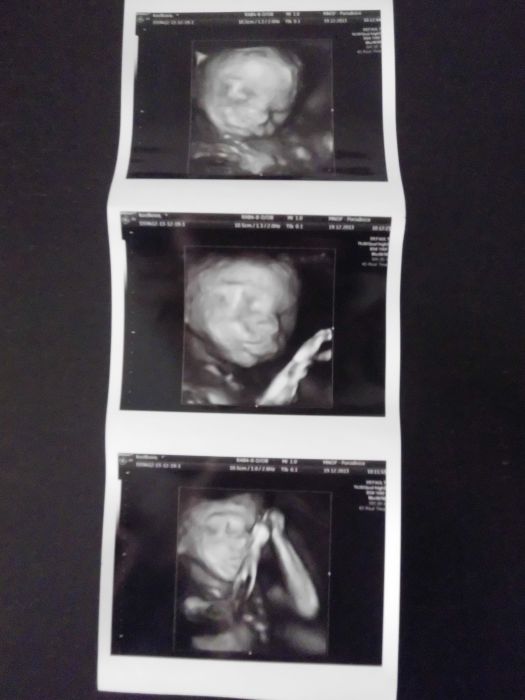

Krása, krása, krása :-) 3D dopadlo úplně perfektně, malá se krásně natočila, spolupracovala :-) Aspoń něco za to čekání :-D Dokonce jsem uronila i slzičku (no trochu víc) jak jsem ji poprvé viděla :-)

Autor: Bluumy 19.12.2013 v 13:52

no je krásná

taky se mi zalily očka, když jsem ten náš poklad poprvé viděla